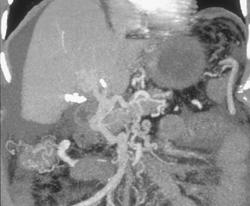

Diagnosis

Lymphoma